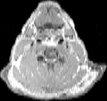

Visible Human male: Sectio transversalis 1234

CT

NMR

Pd T1 T2